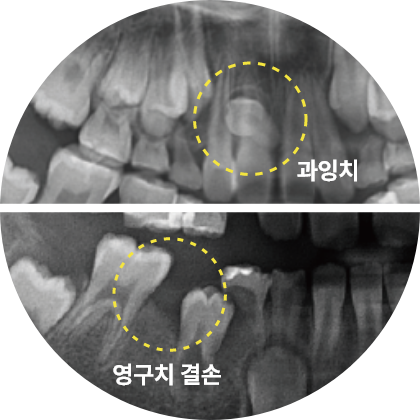

예방교정

적절한 시기의 교정으로 아이의 치아를 건강하게!

이 시기에 교정 검진을 받으면, 성장과 발달을 고려한 적절한 치료 계획을 세울 수 있습니다. 적절한 시기에 치료하지 않으면 나중에 교정의 난이도가 높아질 수 있어, 빠른 시일 내에 교정 검진을 받는 것이 중요합니다.